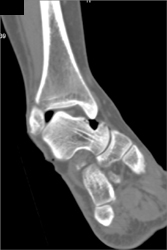

Diagnosis

Tuberculosis (TB) Osteomyelitis T-spine